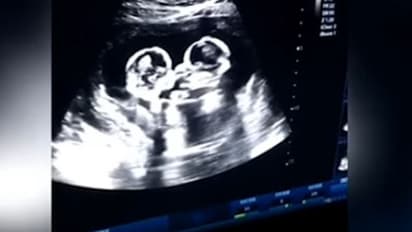

சில சமயங்களில் நம்மை சுற்றி நடக்கும் நிகழ்வுகள் நம்மை வியப்பிலும் ஆச்சரியத்திலும் ஆழ்த்துகிறது. இதே போன்ற ஒரு சம்பவம் தான் சீனாவில் அரங்கேறி உள்ளது. பிறப்பதற்கு முன்பே தாயின் கருவறை உள்ளேயே... இரட்டை குழந்தைகள் அன்பாக சண்டையிடும் காட்சி, ஸ்கேன் செய்தபோது தத்ரூபமாக படம் பிடிக்கப்பட்டுள்ளது. இதனை கண்டு மருத்துவர்கள் மட்டுமின்றி தாயும் இன்ப அதிர்ச்சி அடைந்துள்ளார்.

சீனாவை சேர்ந்த பெண் ஒருவர் நிறை மாத கர்ப்பிணியாக இருந்த நிலையில், அவரின் கருவில் உள்ள குழந்தைகளின் ஆரோக்கியத்தை பரிசோதனை செய்வதற்காக மருத்துவர் ஸ்கேன் செய்துள்ளார்.

அப்போது தாயின் வயிற்றில், இருந்த இரட்டை குழந்தைகள் ஒன்றோடு ஒன்று, அன்பாக சண்டையிட்டுள்ளது. இதனைக் கண்ட மருத்துவர் இன்ப அதிர்ச்சியில் உறைந்தார். மேலும் இந்த காட்சியைப் பதிவு செய்து இக்குழந்தையின் பெற்றோருக்கும் காட்டியுள்ளார்.

தற்போது இந்த பெண், இரண்டு குழந்தைகளையும் பிரசிவித்துள்ளார். குழந்தைகளுக்கு செர்ரி மற்றும் ஸ்ட்ராபெர்ரி என்று பெயரிடப்பட்டுள்ளது. மேலும் வயிற்றுக்குள் சண்டையிட்ட குழந்தைகளின், வீடியோ காட்சியம் வைரலாகி அனைவரையும் ஆச்சர்யப்படுத்தி வருகிறது.